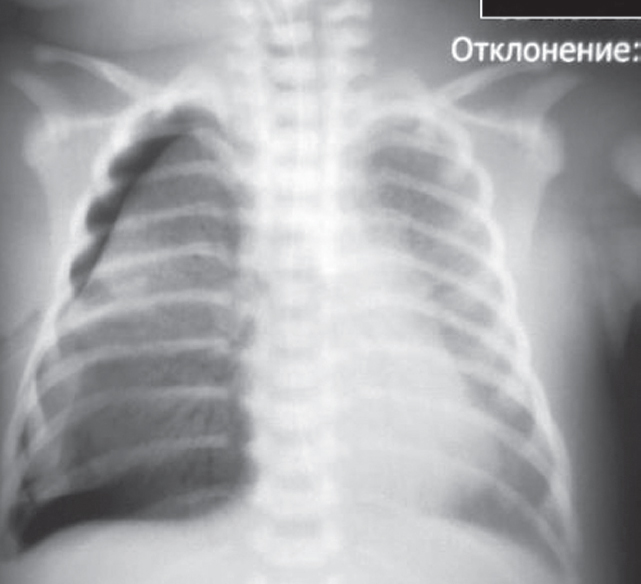

Состояние ребенка с рождения средней степени тяжести, обусловленное явлениями респираторного дистресса (умеренное втяжение межреберий, стонущее дыхание, тахипноэ до 60 в минуту), что потребовало проведения неинвазивной искусственной вентиляции легких (ИВЛ, nСРАР — nasal continuous positive airway pressure) c первых минут жизни [2]. На рентгенограмме отмечаются признаки транзиторного тахипноэ новорожденного (рис. 1).

Рис. 1. Рентгенограмма органов грудной клетки новорожденного с клиническими признаками респираторного дистресс-синдрома через 2 ч после рождения

Fig. 1. Chest X-ray of newborn with clinical signs of respiratory distress 2 hours after birth